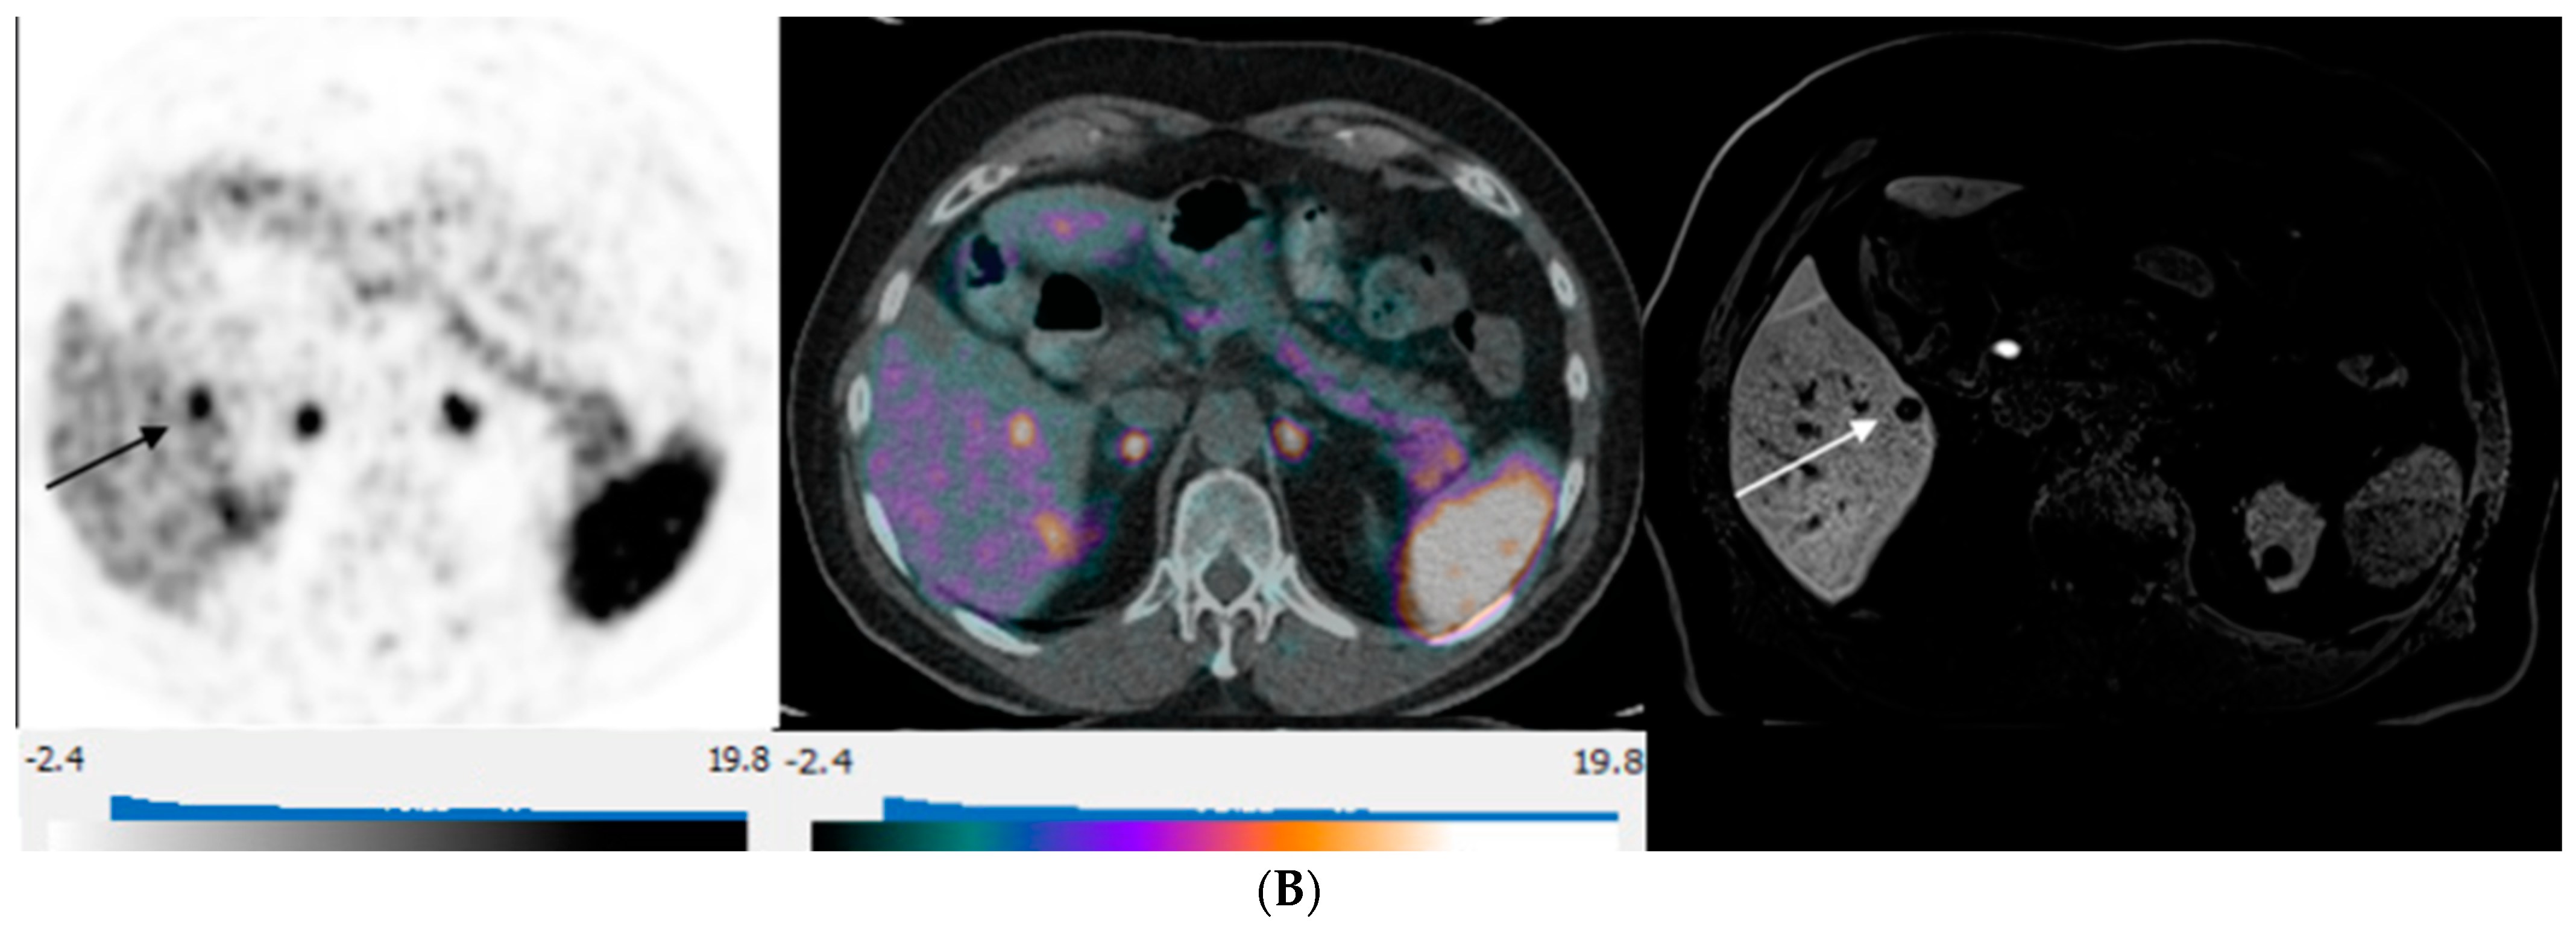

Figure 3.

80-year-old man with well-differentiated G2 small bowel neuroendocrine tumor referred for restaging. 68Ga-DOTATATE PET/CT and Hepatobiliary-specific contrast-enhanced MR show a similar number and distribution of metastases. (A) Axial 68Ga-DOTATATE PET (left), fused PET/CT (middle), and corresponding hepatobiliary phase T1 VIBE image (right) show intense focal radiotracer uptake (arrows) in two small segment 8 metastases. (B) Axial 68Ga-DOTATATE PET (left), fused PET/CT (middle), and corresponding hepatobiliary phase T1 VIBE image (right) show intense focal radiotracer uptake in a small segment 5 deposit (arrows).

Equal NLM counts between DT-PET and pMR were observed in 14 patients (14/30, 47%) (Figure 3). A greater number of deposits were identified on pMR in 12/30 patients (40%), and a greater number of metastases were detected on DT-PET in 4/30 (13%) of patients. Overall, for the entire patient population, pMR detected more metastases than DT-PET (p = 0.01). Of the 12 patients with a greater count of liver metastases on pMR, there were 4 patients in whom multiple deposits were seen on pMR but only 0–1 lesions on DT-PET (Table 4 and Figure 4). All four patients had tumors that were grade 2 or 3 with a Ki 67 index of 5–30%. When these four patients were excluded, no significant differences were found between the number of lesions detected on pMR versus DT-PET (p = 0.10).